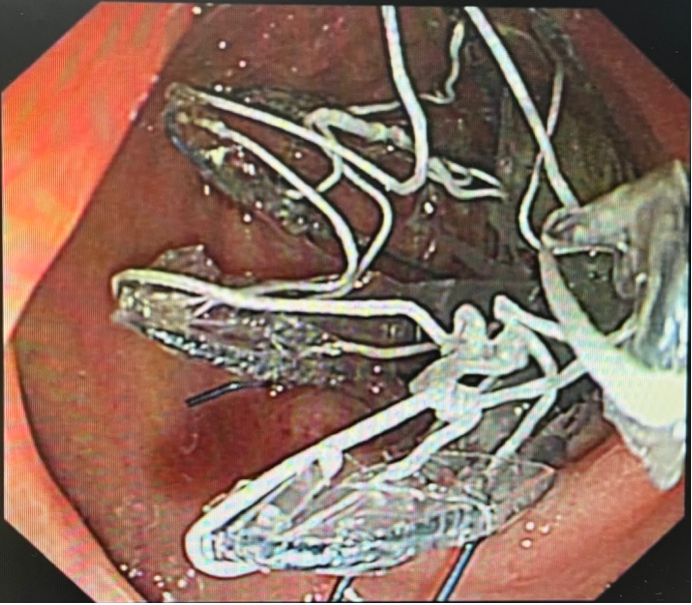

内镜下支架置入操作

这项技术的原理听起来很神奇,但实际上非常巧妙。医生通过胃镜,将一个长约60厘米的生物膜管支架放置在十二指肠和空肠上段,如同在消化道内修建了一条“代谢捷径”,使食物经此通道直接进入小肠中段,隔绝食糜和肠粘膜,减少小肠绒毛上皮细胞对营养的吸收。而胆汁和胰液则在支架外和肠壁之间流动,至膜管末端,两者才开始接触和混合进行消化,从而实现可控的吸收不良效果。